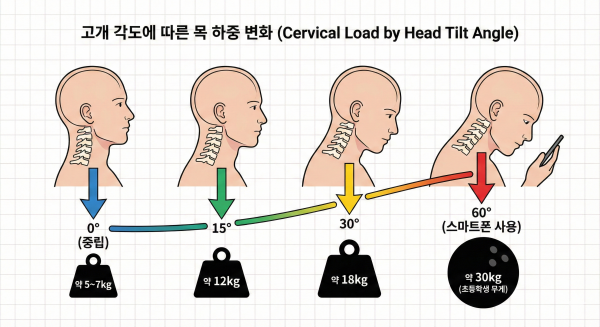

우리의 목은 똑바로 서 있을 때 약 5~7kg의 하중을 견딥니다.

하지만 고개를 숙일수록 그 무게는 기하급수적으로 늘어납니다.

15도만 숙여도 무게는 2배가 되고, 60도까지 숙이면 무려 30kg의 하중이 목에 가해집니다.

이는 초등학생 아이 한 명을 머리에 이고 있는 것과 같습니다.